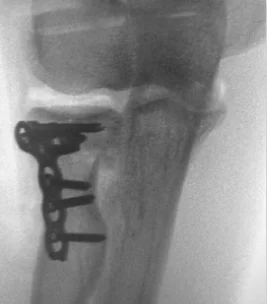

Fracture Distal Humerus

- Treated by open anatomical reduction and internal fixation by plates and screws

- Early mobilization to prevent elbow stiffness